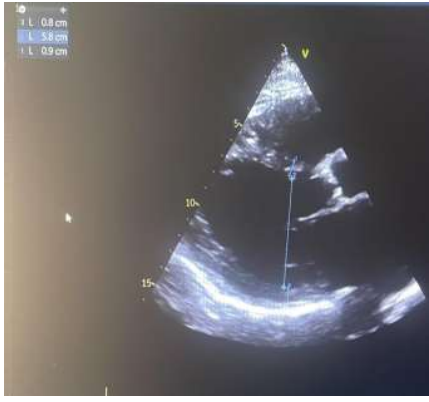

Coronary angiography showed normal coronary arteries (figure 3). Extensive investigations have shown no findings supporting endocrine, metabolic, infectious, or toxic etiologies of cardiomyopathy.

Figure 3: A coronary angiography without significant lesions